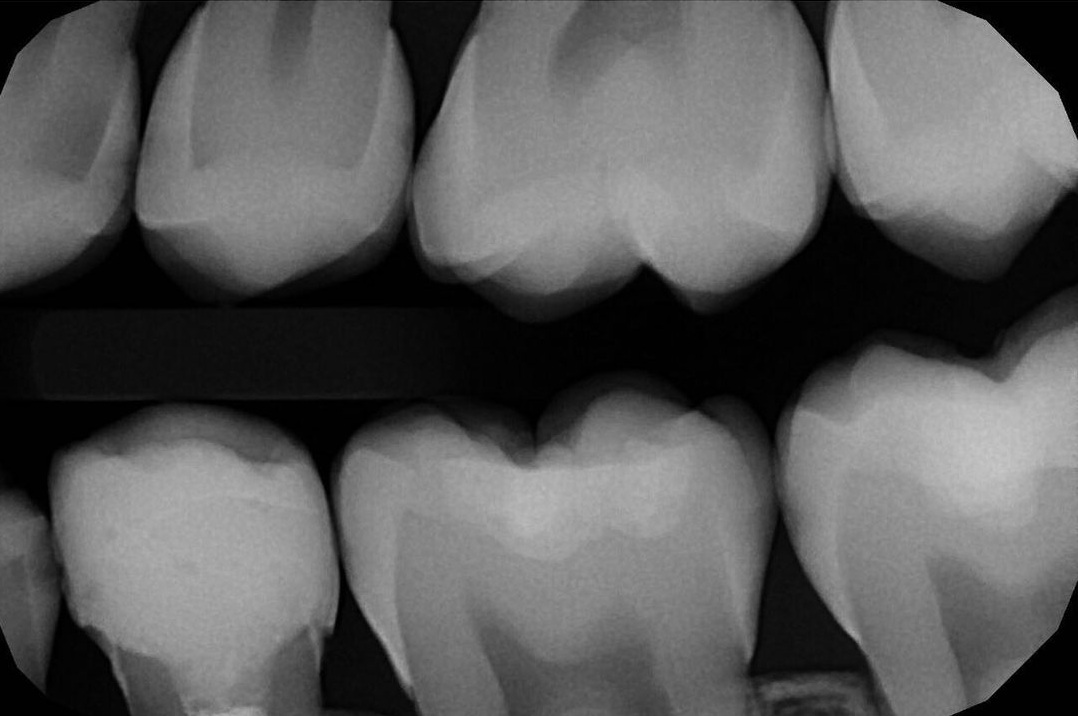

Смотрите, вот зуб на платке, изолирующем его от слюны (к другой стороне зуба всё ещё прикреплён пациент):

image

Видите? Канал чистый.

Пример про платок

Эта штука называется или коффердам, или раббердам. Пластина из латекса, которая изолирует зуб от слюны, воздушных течений изнутри пациента и так далее. Это та самая изоляция, за отсутствие которой в США можно подавать на стоматолога в суд. Если вы после вмешательства по зубному каналу поняли, что такой пластины не было и работал он «по живому», то можете смело засудить его на несколько миллионов рублей почти со стопроцентным шансом.

Угадайте, как часто его используют в России.

И это при том, что есть прямые исследования того, насколько он уменьшает побочные эффекты разных вмешательств. И ладно бы он просто их уменьшал, мы же любим рисковать и готовы терпеть боль за экономию в 10–15 тысяч рублей, правильно? Можно добавить, что это вмешательство принципиально другого качества: например, с ним виниры не отваливаются, качество адгезивной фиксации на порядок выше.